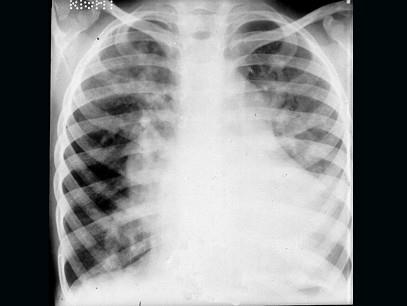

问题 患儿男,4岁,生后反复发生呼吸道感染,发育差,活动后气促,无发绀。听诊胸骨左缘第3肋间可闻及Ⅲ级粗糙的全收缩期杂音,肺动脉第2音显著亢进,X线示如图:肺野明显充血。该患儿最易并发下列哪种疾病 ( )

选项 A、脑脓肿 B、喉返神经麻痹 C、支气管肺炎 D、脑栓塞 E、心肌炎

答案 C